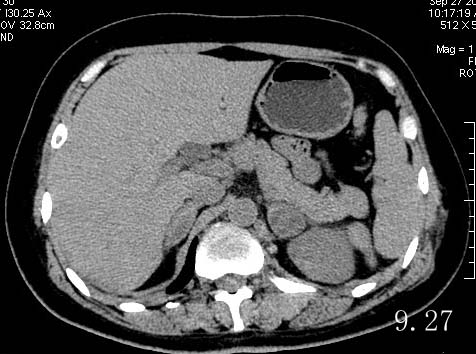

女,47岁,9.7车祸后,肾上腺出血,9.27复查

9.7车祸i受伤,之前无任何症状。从ct片上看,9.27与9.7相比,其高密度吸收。

很明显是左肾上腺区一个类圆形病灶,边缘清晰,九月七日内见新月形或半月形高密度出血灶,到九月二十七日液化成低密度,这是包膜下的一个大血肿.如果没有治疗后再次复查病灶吸收缩小或手术证实的话,很难区分肾上腺囊肿或腺瘤合并出血.

双侧肾上腺均有占位,都是出血吗?9月7日与27日片不是同一层面,应再多提供几幅图片。

双侧肾上腺肿块,应该不只是出血这么简单。tb?肿瘤?如果3次ct检查都测量病变区ct就好了。我感觉肾上腺病变是实质性的,搜索一下肺部改变或许有帮助。

我怎么觉得双侧肾上腺区都有占位啊。难道都是出血吗?另外肾上腺出血应该肾上腺区模糊啊,肾上腺没有包膜所以出血应该没有固定外形啊。希望楼主能提供有力的证据

不太典型,双侧肾上腺占位,腺瘤可能性大,左侧合并出血;结合临床随访